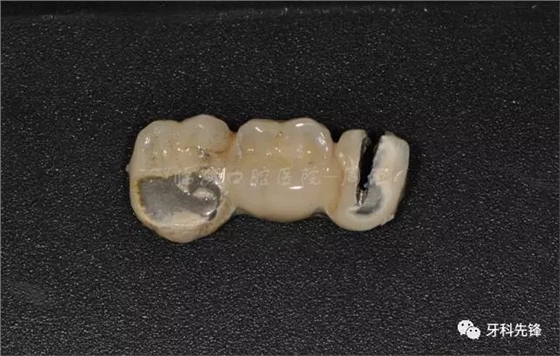

圖7原烤瓷冠修復(fù)體